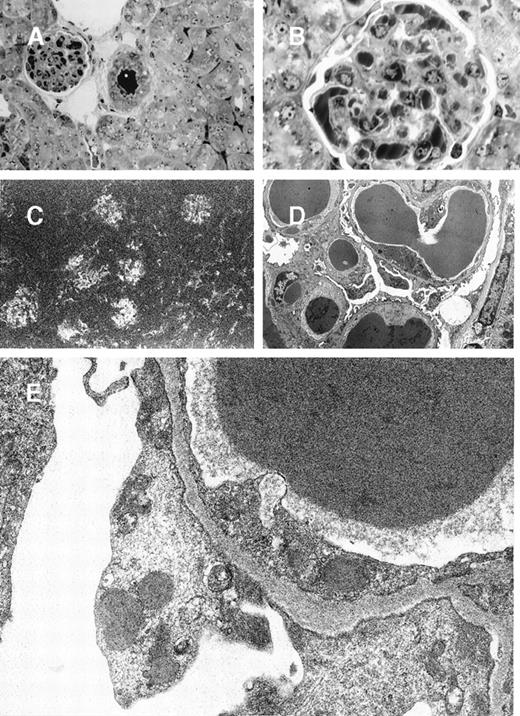

Glomerular lesions in 8A4 mice kidneys.

(A and B) Light microscopy showing the proliferative and exudative changes (A, original magnification ×200, light green trichromic staining) and the voluminous depositions of material predominantly in mesangial and subendothelial areas (B, original magnification ×1000, semi-thin section, toluidine blue staining). (C) Immunofluorescence microscopy with antimouse Ig conjugate (original magnification ×200) showed intense staining of deposits strictly limited to glomeruli without any staining of peritubular capillary lumen. (D and E) Electron microscopy showed osmiophilic deposits in mesangial and subendothelial spaces (wire-loop lesion) with few subendothelial deposits. The glomerular capillary lumens were free of deposits (D, original magnification ×5000). Note the highly organized crystalline glomerular deposits formed by densely packed microtubules (external diameter = 12 nm) in transversal section and parallel arrays in longitudinal section with a 12-nm striation periodicity (E, original magnification ×60 000).

In 8A4 mice, light microscopic examination of tumor biopsies showed abundant crystal inclusions similar to Ig crystals observed in cultured cells (Figure 3). Contrasting with the absence of a monoclonal peak, kidney samples showed marked glomerular lesions with abundant wire-loop deposits along the glomerular basement membrane, predominating in mesangium on the endothelial aspect of the basement membrane and often resulting in pseudo-thrombi (Figure4A and 4B); to a lesser extent, deposits were also found on the epithelial side and occasionally invaded the urinary space. In some glomeruli, Ig deposits were associated with endocapillary proliferation and polymorphonuclear leukocyte infiltration. By immunofluorescence, deposits strongly stained with an antimouse IgG and were present within all glomeruli (Figure 4C). No deposits were found in other locations of the kidney or in liver or spleen. Electron microscopy also confirmed the crystalline nature of extracellular renal deposits by demonstrating their regular striation of 12- to 14-nm periodicity (Figure 4D and 4E). The crystals observed in vitro in cultured cells (Figure 1) and in vivo in tumoral cells (Figure 3), either by immunofluorescence staining or by electron microscopy, were identical to those formed in animals as kidney deposits (Figure 4).